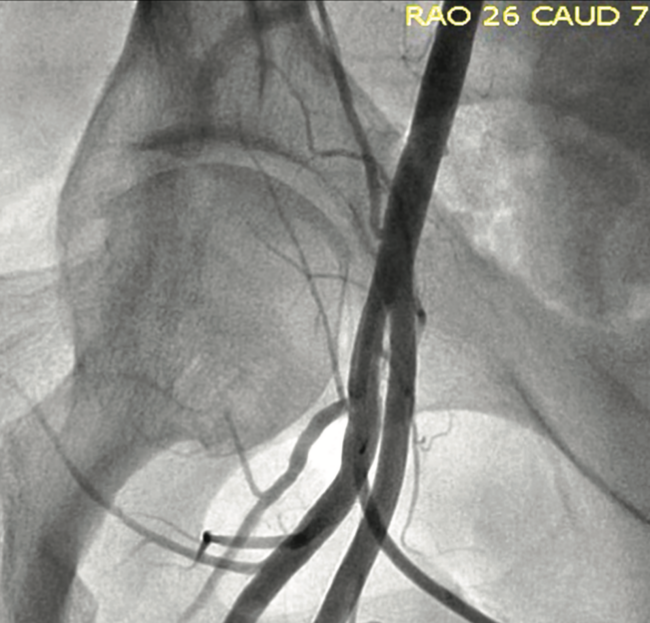

Arteriovenous Fistula Mimicking Pseudo-Complication From Femoral Vascular Access for Cardiac Catheterization

An arteriovenous (AV) fistula is an abnormal connection between a vein and an artery. This type of abnormal communication leads to redirection of the blood from the artery to the vein, which is from a high-pressure system towards a low-pressure system. As a result, distal capillary circulation will have decreased arterial blood supply that may lead to tissue ischemia. Any tissue ischemia, in turn, may lead to tachycardia and rarely, high-output heart failure due to a compensatory increase in the stroke volume and cardiac output from decreased peripheral vascular resistance.1-3 Duplex ultrasonography usually can identify the extent, velocity, and flow within AV fistulas.4 Indications for ultrasound-guided compression or surgical closure of an AV fistula include extremity swelling or tenderness, congestive heart failure, significant shunting, and deep venous thrombosis.2-4